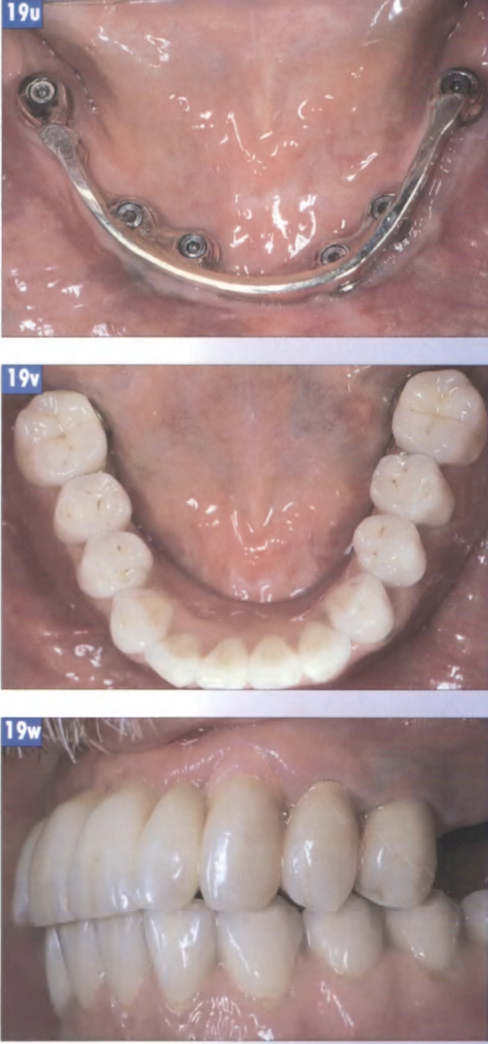

Рис. 19r.

Готовая реставрация с соединительным элементов типа балка-замок: вид со стороны поверхности окклюзии.

Рис. 19s.

Задвижной замок в открытом состоянии.

Рис. 19t.

Готовый протез нижней челюсти: вид спереди.

Рис. 19и.

Зеркальный снимок первичной балки in situ: вид со стороны поверхности окклюзии.

Рис. 19v. Ситуация после фиксации протеза: вид со стороны поверхности окклюзии.

Рис. 19w. Промежуточный результат: новая реставрация с соединительным элементом балка-замок на нижней челюсти и временная реставрация длительного ношения (облицована полимерными материалами) на верхней челюсти.